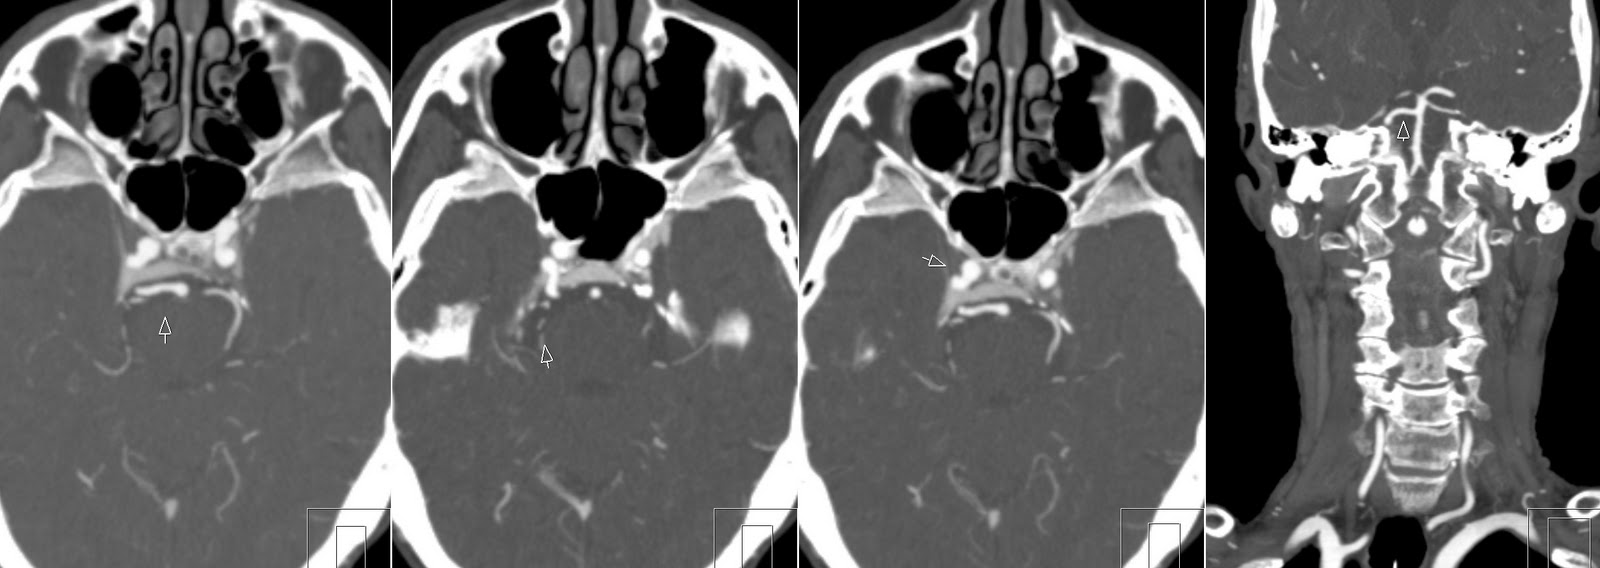

CT Angio images show how PTA exits basilary artery, enters cavernous sinus and anastomoses with internal carotid artery.

Persistent Trigeminal Artery represents carotid-vertebrobasilar anastomosis connecting basilar artery with internal carotid artery (ICA). Reported incidence is 0.1–0.6%. There are two types: Saltzman 1 (this case) with absent posterior communicating artery. And Saltzman type 2 when ipsilateralt posterior cerebral (PCA) artety arises directly from ICA and P1 segment is absent (fetal origin of PCA).